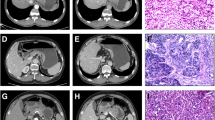

Supplementary Fig. 1.

82-year-old woman with gastric signet ring cell carcinoma of (SRC).(A)Iodine concentration in venous phase(ICvp),IC = 3.2 mg/ml;standardized iodine concentration(NICVP),NIC = 0.80;(B)the slope of energy spectrum curve(kVP),k = CT40keV-CT100keV/100 − 40 = 300.6–75.5/60 = 3.75

Supplementary Fig. 2.

57-year-old man with gastric mixed signet ring cell carcinoma(mSRC).(A)Iodine concentration in venous phase(ICVP),IC = 2.4 mg/ml;standardized iodine concentration(NICVP),NIC = 0.44;(B)the slope of energy spectrum curve(kVP),k = CT40keV-CT100keV/100 − 40 = 245.7–69.9/60 = 2.93

Supplementary Fig. 3.

80-year-old woman with gastric non signet ring cell carcinoma(nSRC).(A)Iodine concentration in venous phase(ICvp),IC = 1.6 mg/ml;standardized iodine concentration(NICVP),NIC = 0.43;(B)the slope of energy spectrum curve(kVP),k = CT40keV-CT100keV/100 − 40 = 202.5–67.2/60 = 2.26